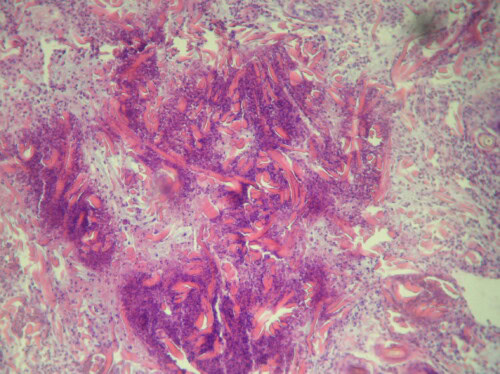

Photo 4 : examen histopathologique d’un cas de CGE : présence de « figures en flamme »

Des examens cytologiques multiples sont réalisés par apposition sous-crustacée. Leur examen microscopique montre une population inflammatoire, avec une prédominance de polynucléaires éosinophiles (photo 3). Des biopsies cutanées sont réalisées sous anesthésie générale. L’examen histopathologique (photo 4) montre une infiltration diffuse du derme superficiel et moyen, par une population bigarrée, mais à nette prédominance de polynucléaires éosinophiles. Sont également notés des mastocytes nombreux et quelques lymphoplasmocytes. La présence d’images de dégénérescence des fibres de collagène est associée. Aucun élément figuré n’est observé et en particulier aucune inclusion virale n’est visualisée. Un diagnostic de lésion du complexe granulome éosinophilique est proposé par l’histopathologiste. Un prélèvement biopsique de la lésion, conservée dans du liquide physiologique, est envoyée à un laboratoire pour recherche par technique PCR de virus, et s’avèrera positive à un titre élevé pour l’herpèsvirus félin. Les recherches de rétrovirus par sérologie et sur la pièce biopsique par PCR sont négatives.